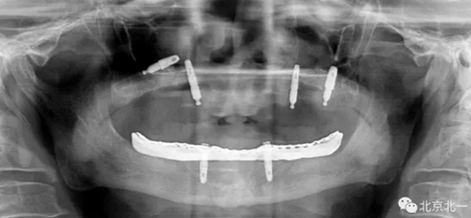

圖三:植體負重一年后脫落掉入上頜竇,

3.png

圖四:王明老師接手時植體往后移位,

4.png

圖五:北一種植王明老師出馬,采用外側(cè)壁開窗微創(chuàng)取出術(shù)。

5.png

總結(jié):植體脫落得原因很多,最常見的因素有感染或者污染,植體自動松動,沒有骨結(jié)合,過早負重,導致植體在沒有完全骨結(jié)合后受力過大脫離, 或者植體在常規(guī)負重后一年內(nèi)脫落,可能因為咬合設(shè)計不合理,或者種植體維護不到位等因素,病人自身因素也是一個不可忽視的因素,某些系統(tǒng)性疾病等。